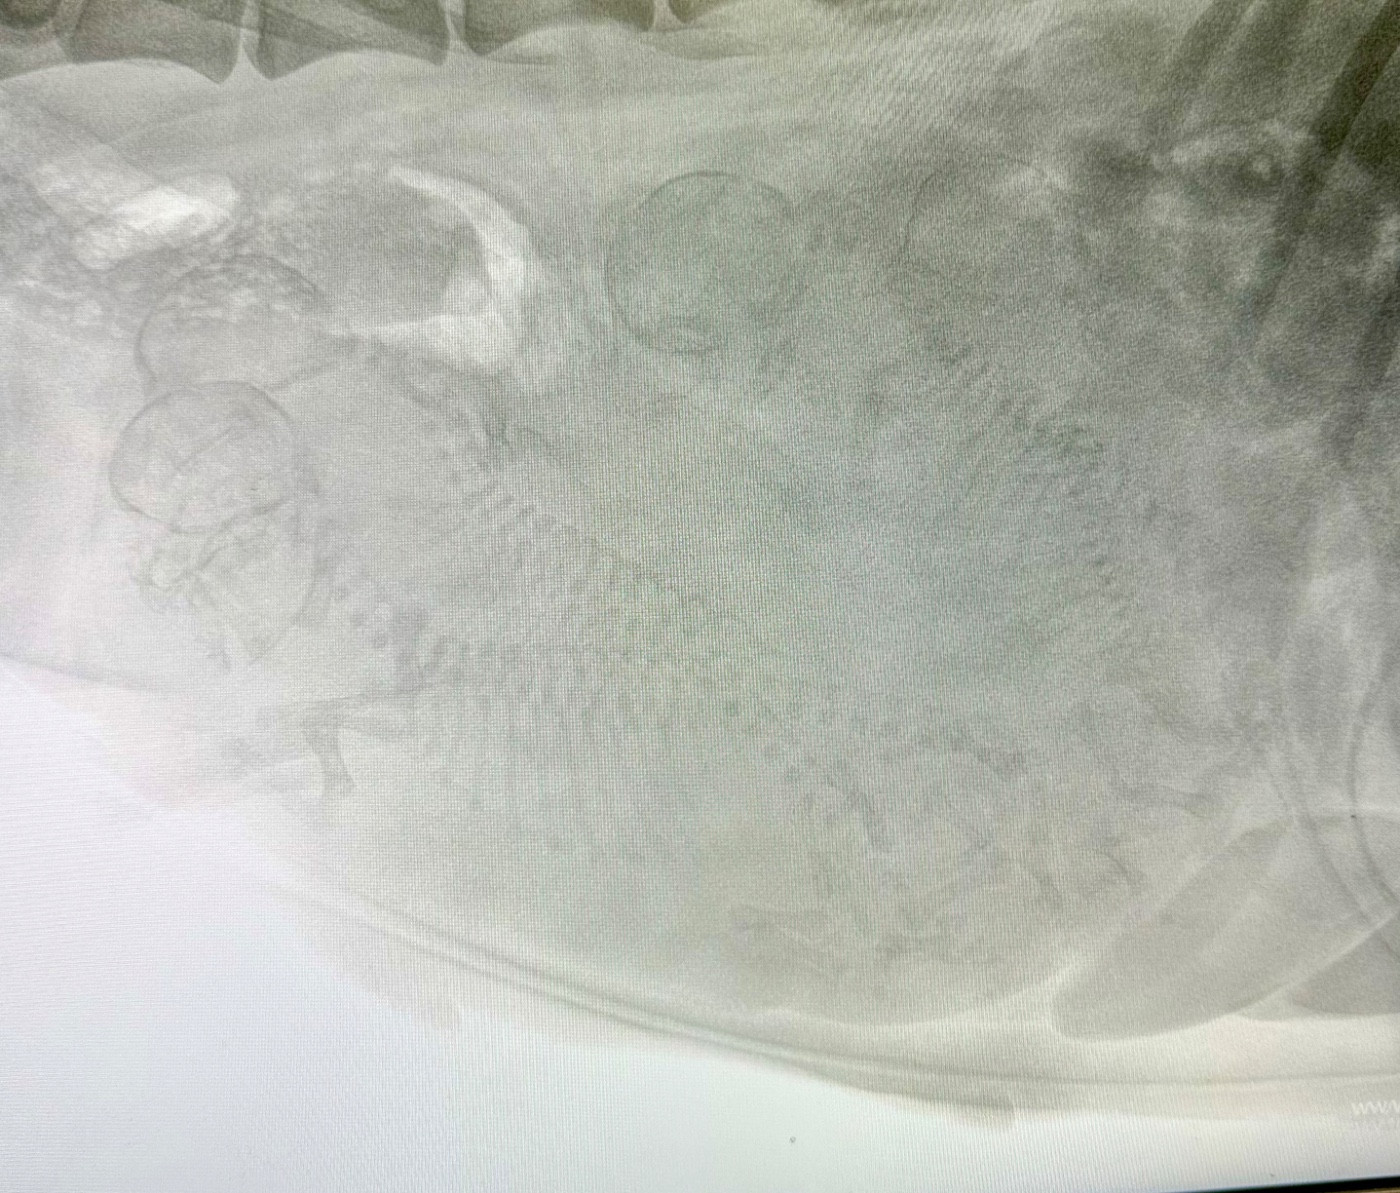

Entey Zipangu X Kuemdol of Daijen

Le mariage

Radio de comptage